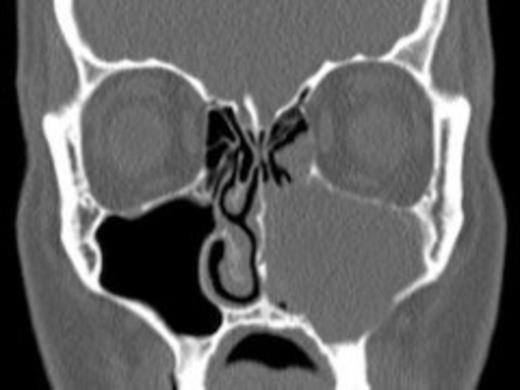

Axial computed tomography scans with coronal reformats were acquired through the paranasal sinuses. This demonstrated obstruction of the left nasal airway. There was complete opacification of the left maxillary sinus with obscuration of the osteomeatal complex. Expansion and thinning of the medial wall of the maxillary antrum was also noted. The remaining paranasal sinuses were clear. The postnasal spaces were equal and symmetrical and there was no evidence of focal bony destruction.

The radiological findings correlated with the clinical observations and the patient underwent Functional Endoscopic Sinus Surgery (FESS) to drain the large septic collection in the left maxillary antrum.